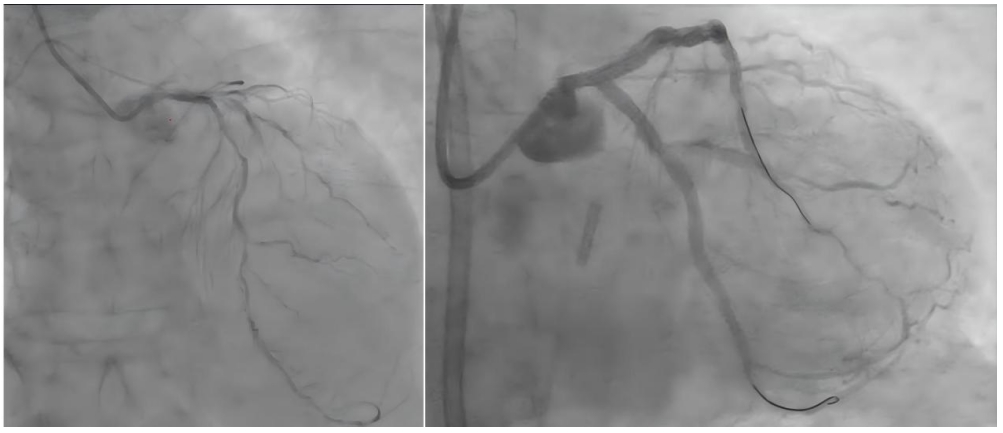

患者唐先生因持续胸痛入院,被确诊为急性非ST段抬高型心肌梗死,冠脉造影结果显示其冠状动脉严重三支病变伴重度钙化,尤其是左主干弥漫性狭窄高达80%~90%,情况极为危急。

左主干作为心脏供血的“总闸门”,若不及时干预,将直接威胁患者生命。面对如此复杂的病情,一般多建议外科搭桥手术,但经患者及家属的慎重考虑,最终选择了信任南华大学附属南华医院心血管内科介入团队。

面对这块“硬骨头”,由医院党委委员、副院长马小峰带领的介入团队制定了周密方案。团队迎难而上,采用高难度冠脉旋磨术,如同用“金刚钻”打磨瓷器一般,先将坚如磐石的钙化斑块击碎,再顺利植入药物涂层支架重建血运。

▲术前(左)与术后(右)影像